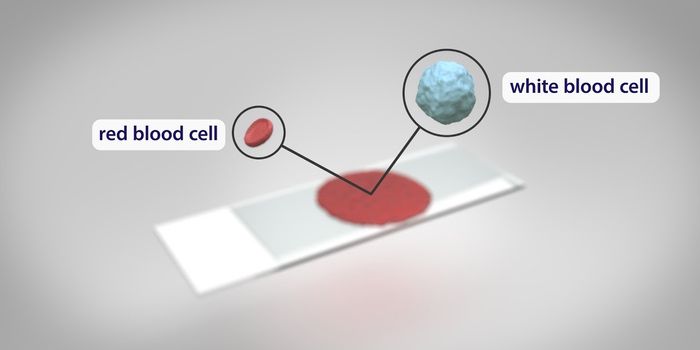

DEC 09, 2017VideosBlood donation is essential; hospitals rely on donors to maintain a healthy blood supply to help patients. Both whole bl ...